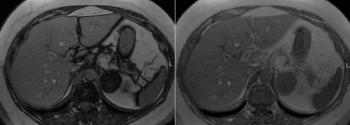

Adrenal Lesion Discovered in 50-Year-Old PatientPublished: August 12th 2013 | Updated: